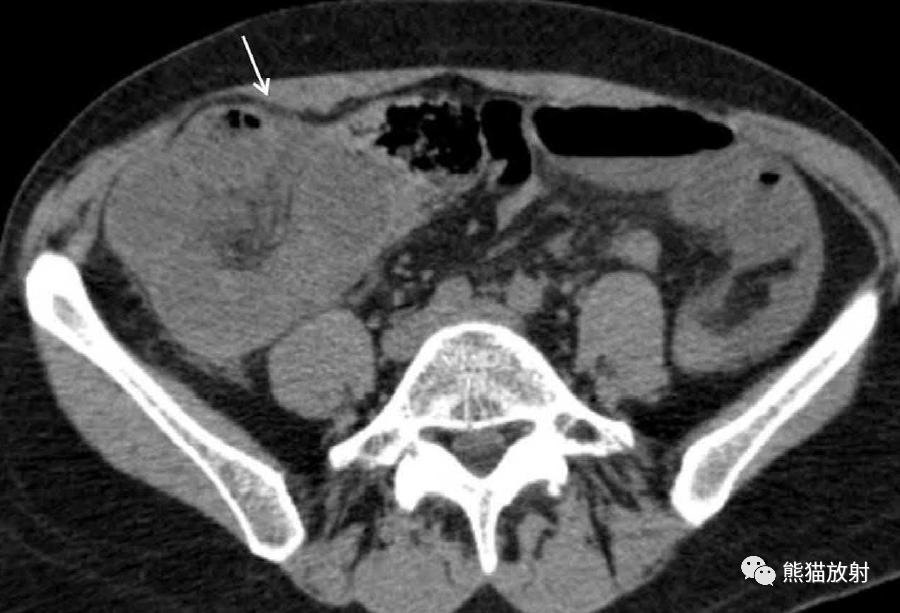

肠系膜疝。 扩张、充满液体的小肠襻丛位于前腹壁下的升结肠侧旁(箭),取代网膜脂肪。充盈的血管及邻近肠系膜模糊,反映了小肠绞窄性梗阻。